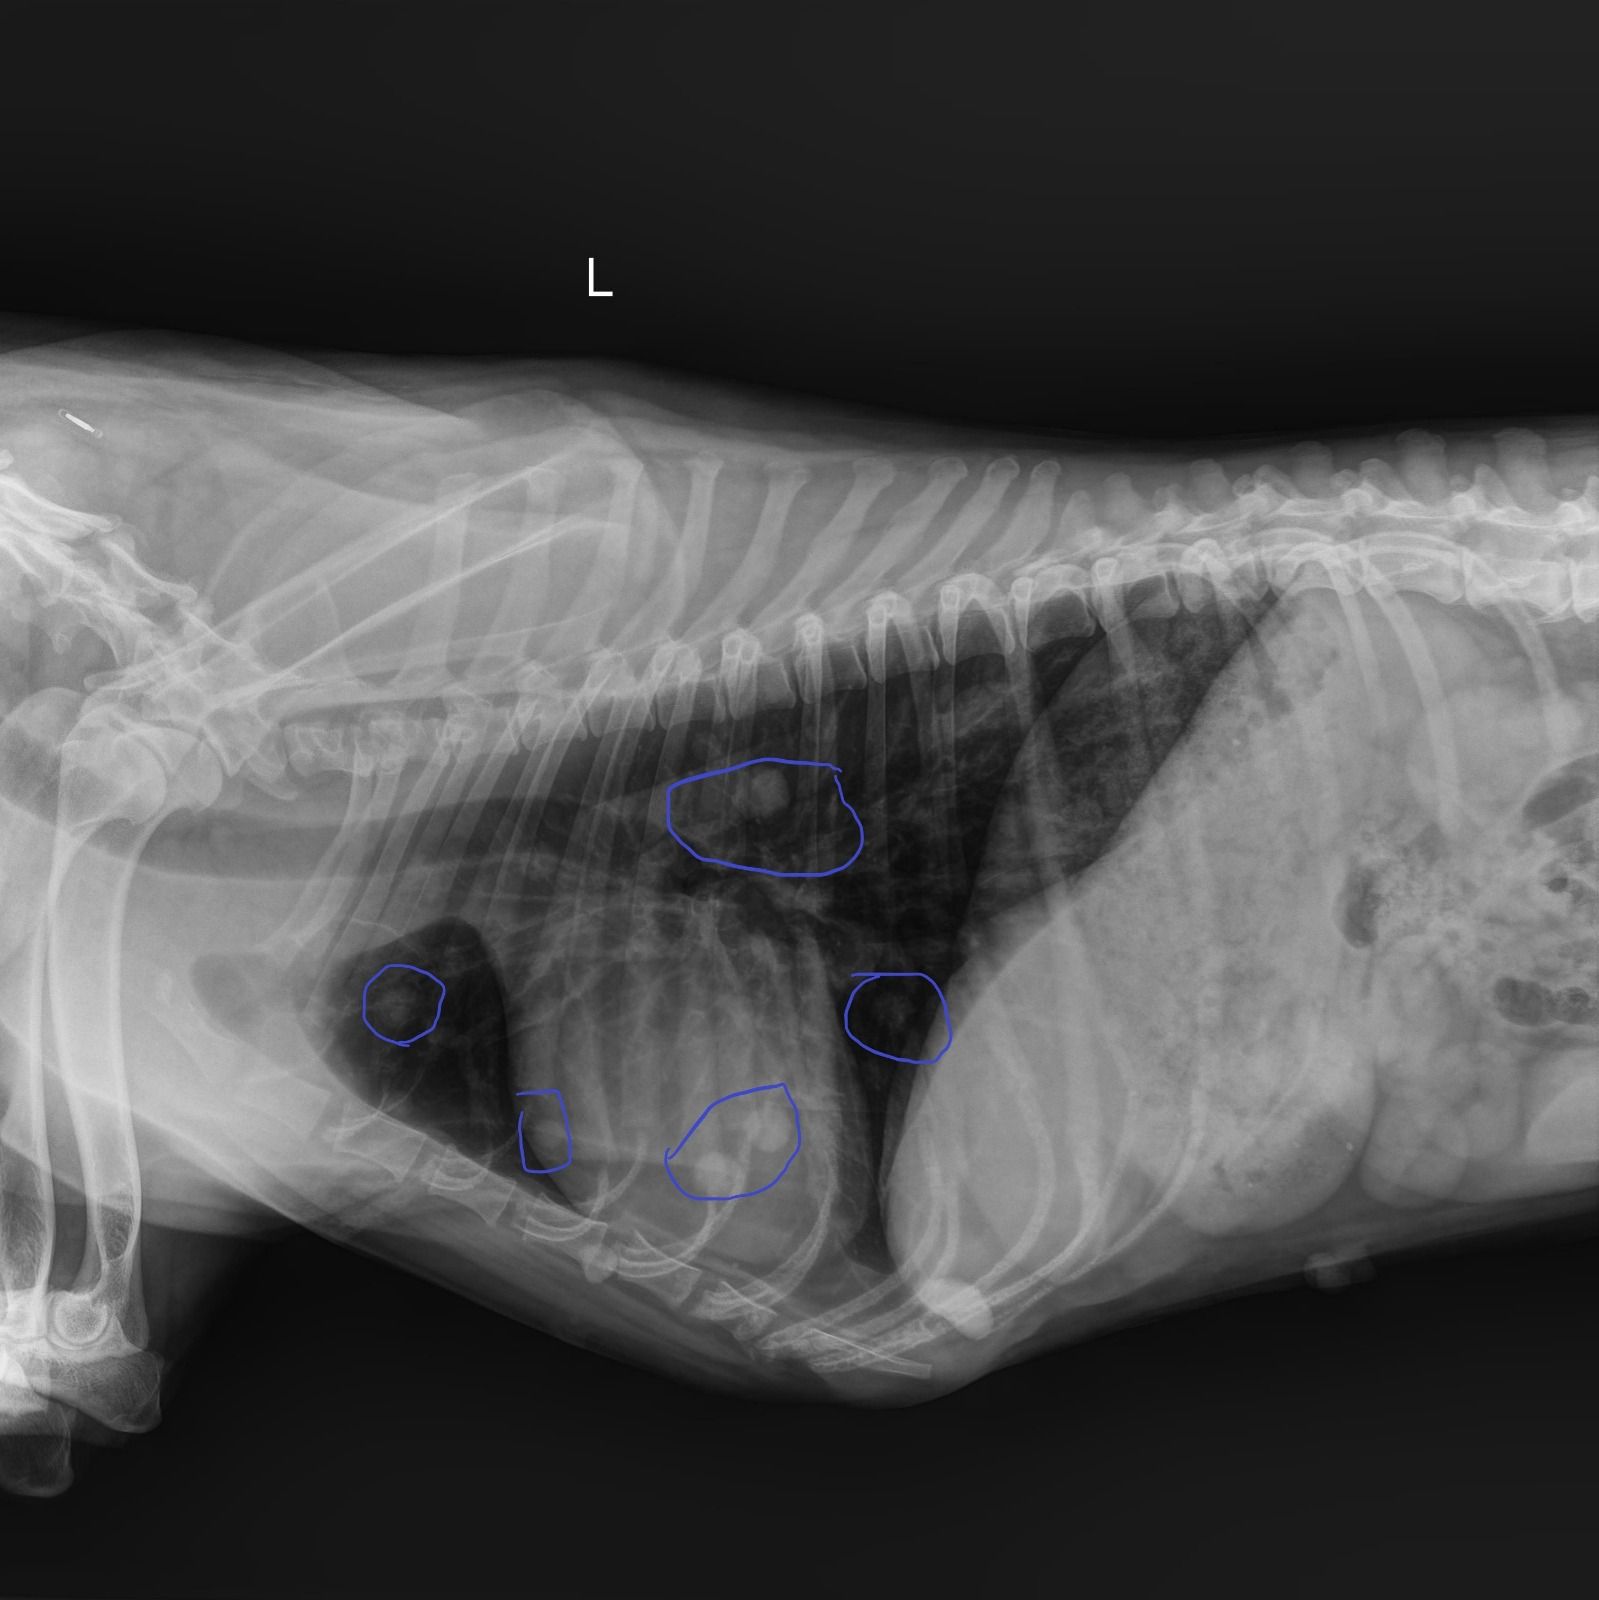

Die Ergebnisse der Röntgenaufnahme sind leider nicht so gut! 😢

Gary hat eine Hüftgelenksdysplasie an beiden Hinterbeinen. Die Köpfe beider Oberschenkelknochen befinden sich außerhalb der korrekten Position, da die Hüftpfanne an anatomischer Tiefe verloren hat. Die Knochen sind ausgerenkt, und können nur auf chirurgischem Wege korrigiert werden, entweder durch Ersatz der Oberschenkelköpfe (dies wird von einem Kollegen in Athen durchgeführt) oder durch Entfernung der Köpfe und die Bildung eines Pseudogelenks (zwei Operationen im Abstand von 3 Monaten, Kosten 650€ pro Operation in unserer Klinik). Da Gary wirklich leidet, müssen diese Operationen sein, also 1300 € kommen hier mindestens auf uns zu.